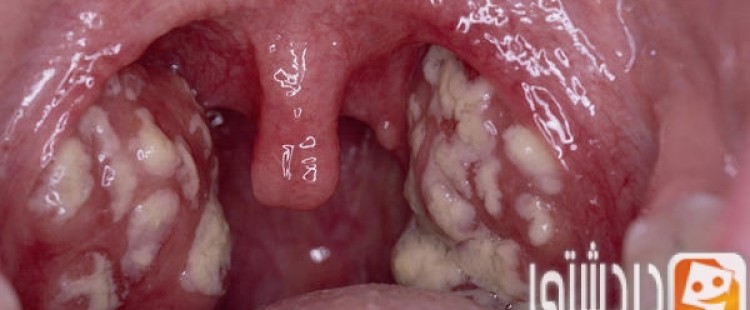

اللوز تعتبر المكان الذي يقع في آخر جوف الحلق، وتنقسم إلى لوزتين، لوزة يمنى ولوزة يسري، تعتبر اللوز خط الدفاع الأول عن الجسم وهي من أكثر المناطق التي تتعرض إلى…